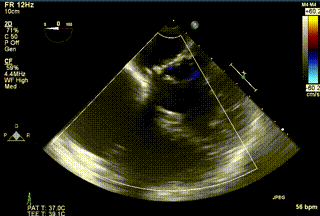

三例患者入院后,葛均波院士團(tuán)隊周達(dá)新教授、潘文志教授、張源博士、陳莎莎博士及心超室的潘翠珍教授、李偉教授對患者的情況進(jìn)行詳細(xì)評估和討論,最終決定為三例患者選擇LuX-Valve Plus40mm、50mm和50mm型號的瓣膜進(jìn)行手術(shù)治療。手術(shù)后即刻拔除氣管插管,術(shù)后患者三尖瓣反流癥狀得到顯著改善,復(fù)查心超結(jié)果顯示人工三尖瓣瓣膜支架固定穩(wěn)定,瓣葉關(guān)閉形態(tài)未見異常,未見明顯反流。

LuX-Valve Plus是LuX-Valve系列產(chǎn)品的第二代,采用的是經(jīng)血管入路的全新輸送系統(tǒng),其設(shè)計開發(fā)過程得到了上海中山醫(yī)院葛均波院士及其團(tuán)隊的精心指導(dǎo),研究結(jié)果提示瓣膜植入的安全性和有效性俱佳,尤其瓣膜獨特的設(shè)計使其具有極佳自適應(yīng)性,本周三例患者病因及解剖結(jié)構(gòu)各具特點,但均可從LuX-Valve Plus植入術(shù)明顯獲益。目前,LuX-Valve Plus已在全國各中心開展救治性臨床研究,相信未來定會為更多的三尖瓣反流患者帶來福音。